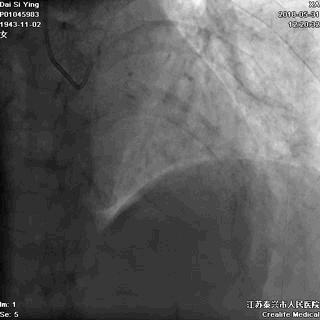

广东佛山有位姓谭的男子,年仅45岁,只身一人出差来江苏泰兴,突发胸痛,9小时后就诊于江苏省泰兴市人民医院,心电图诊断为“急性心肌梗死”。

他在这里举目无亲,该怎么办?

听了医生的建议后,他当机立断,自己签字接受急诊手术。这是一个大胆而又明智的决定!医生立即为谭某进行了介入手术,打开了闭塞的血管,恢复了心肌的血液供应。

闭塞的前降支血管开通了,心肌的血供恢复了

记住:出门在外发生“急性心梗”,如果身边没有亲人,能够救你一命的只有医生!请相信他,果断签字手术。不要等待配偶,不要等孩子,更不要犯傻地要求回当地手术。命运此刻就掌握在你自己手中。